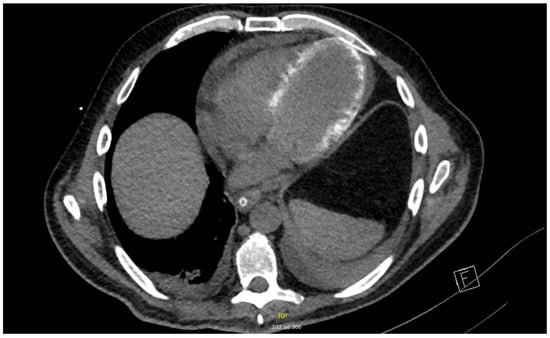

The results of additional investigations that were performed during the resolution phase of disease showed signs consistent with a septic cardiomiopathy. On cardiac CT performed on day 20 in the ICU, a hemodynamically unremarkable pericardial effusion (maximal diameter of 16 mm) and diffuse myocardial calcinations were observed (Figure 2).

Figure 2. Cardiac CT scan with diffuse myocardial calcinations and pericardial effusion, performed on day 20 of ICU treatment (axial image).